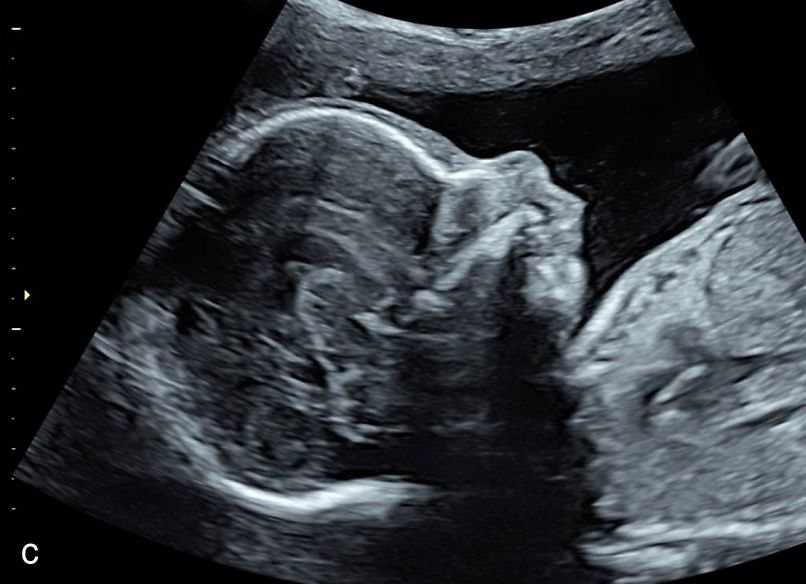

9

Micrognathia at 12 weeks on sagittal (a) and coronal (b) views and at 20 weeks on sagittal view (c).

Micrognathia can be determined subjectively but, more recently, diagnostic indices such as the inferior facial angle (comparing the frontal bone to a line drawn at the angle of the mentum), frontonasomental angle (comparing the frontal bone to a line drawn at the tip of the nose and mentum) and jaw index (comparing the axial mandibular diameter to the anteroposterior distance of the mandible) have been developed.23,24 Micrognathia may be less apparent with continued growth and development, particularly if diagnosed in the first or early second trimester, and therefore evaluation with these diagnostic indices may be particularly useful in these cases, along with careful follow-up.23